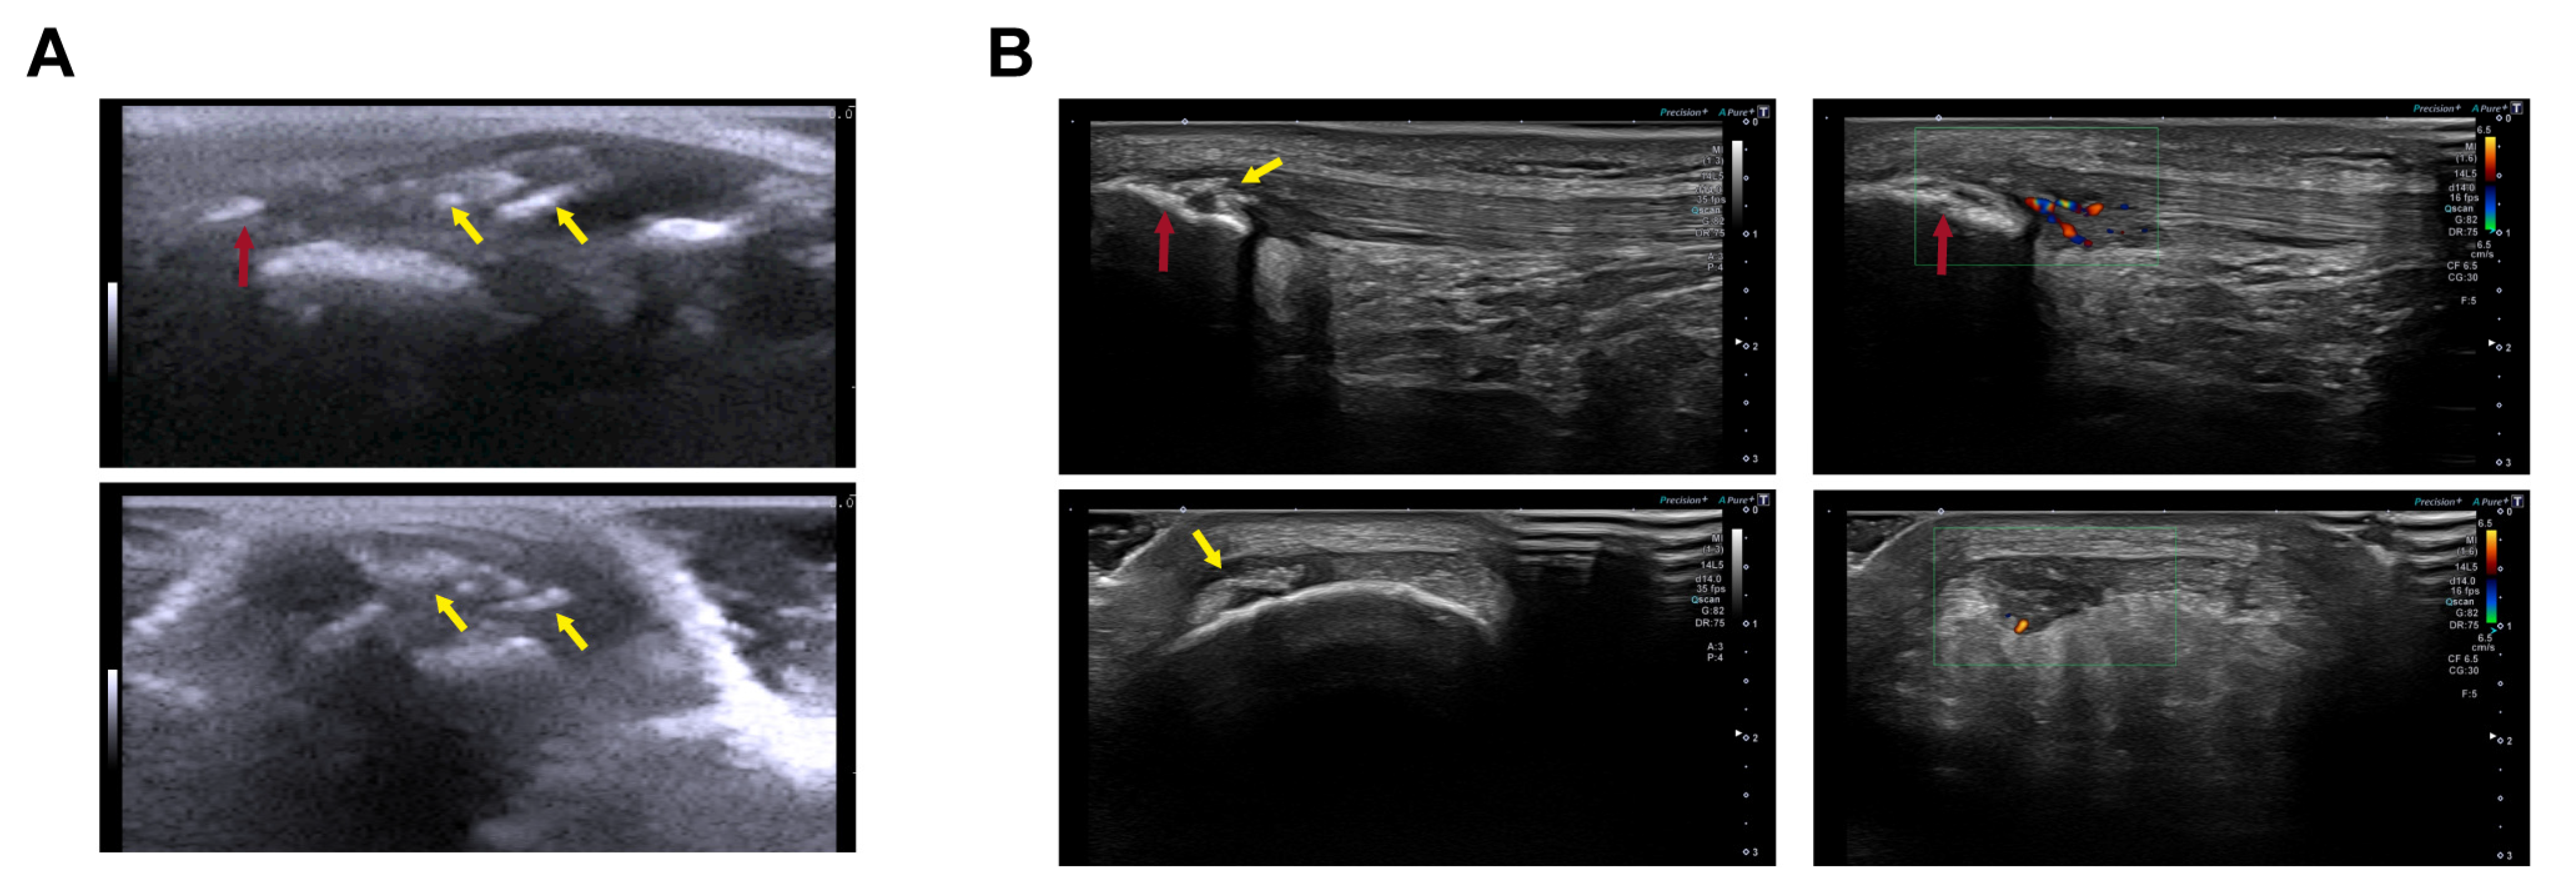

2.2. Ultrasound Clinical Imaging Analysis of the Longitudinal Evolution of Patellar Tendon Injury

4.3. Ultrasound Clinical Imaging Analysis of the Longitudinal Evolution of Patellar Tendon Injury